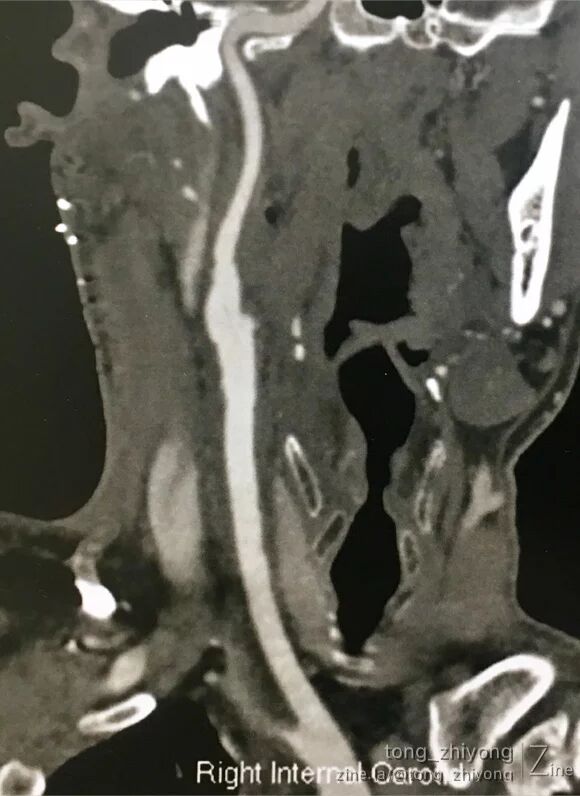

CTA可见:右侧颈动脉重度狭窄,动脉粥样硬化斑块破裂,造影剂进入斑块。

术后一周CTA可见:颈动脉通畅,颈内动脉起始部管径适度增宽。

6. 术后CTA显示:颈内动脉起始部适度增宽。这得益于补片宽度的选择。同时也和术后超声未见涡流信号互相印证;